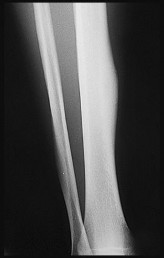

A 32-year-old male sustains a closed tibia fracture and develops intense leg pain out of proportion to the injury. You suspect acute compartment syndrome.

Which of the following pressure parameters is considered the most reliable threshold indication for performing a four-compartment fasciotomy?

Explanation

The differential pressure (Delta P) is universally recognized as more reliable than absolute compartment pressure for diagnosing acute compartment syndrome. A Delta P is calculated by subtracting the intracompartmental pressure from the patient's diastolic blood pressure. A Delta P of less than 30 mmHg represents inadequate tissue perfusion pressure and is an absolute indication for emergency fasciotomy.